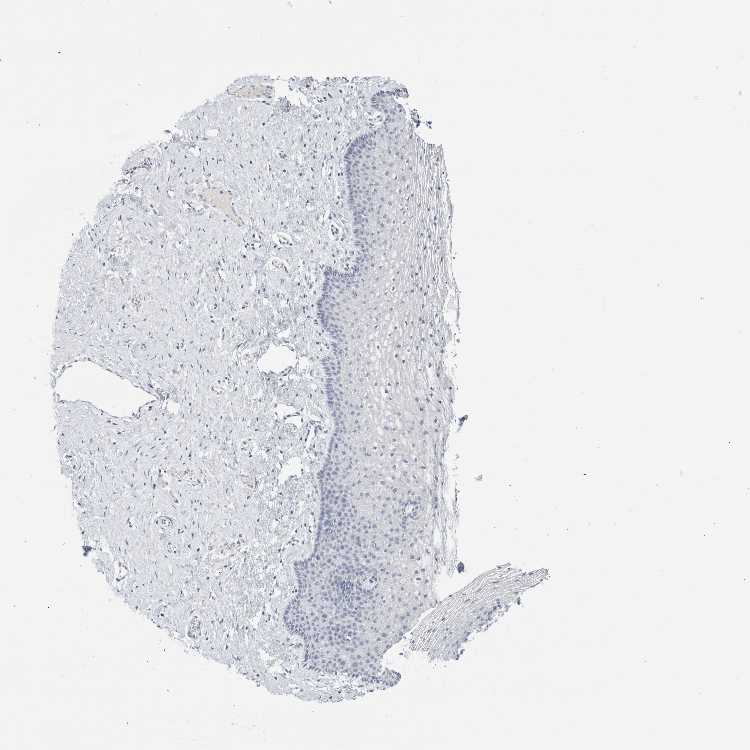

VAGINA - Antibody stainingi

Antibody staining in the annotated cell types in the current human tissue is reported as not detected, low, medium, or high, based on conventional immunohistochemistry profiling in selected tissues. This score is based on the combination of the staining intensity and fraction of stained cells.

Each image is clickable and will lead to virtual microscopy that enables deeper exploration of all samples and also displays staining intensity scores, fraction scores and subcellular localization as well as patient and tissue information for each sample.

Antibody HPA007865Antibody CAB025862

Squamous epithelial cells Not detectedNot detected